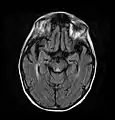

Axial MRI B=1000 DWI image showing hyperintense signal indicative of restricted diffusion in the mesial dorsal thalami

Axial MRI FLAIR image showing hyperintense signal in the periaqueductal gray matter and tectum of the dorsal midbrain